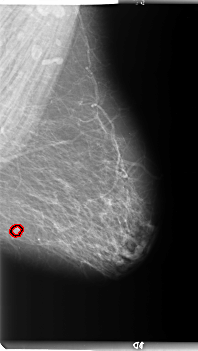

B_3089_1.RIGHT_MLO

FILE: B_3089_1.LEFT_MLO.OVERLAY

TOTAL_ABNORMALITIES 1

ABNORMALITY 1

LESION_TYPE MASS SHAPE ROUND MARGINS ILL_DEFINED

ASSESSMENT 4

SUBTLETY 4

PATHOLOGY MALIGNANT

TOTAL_OUTLINES 1

BOUNDARY